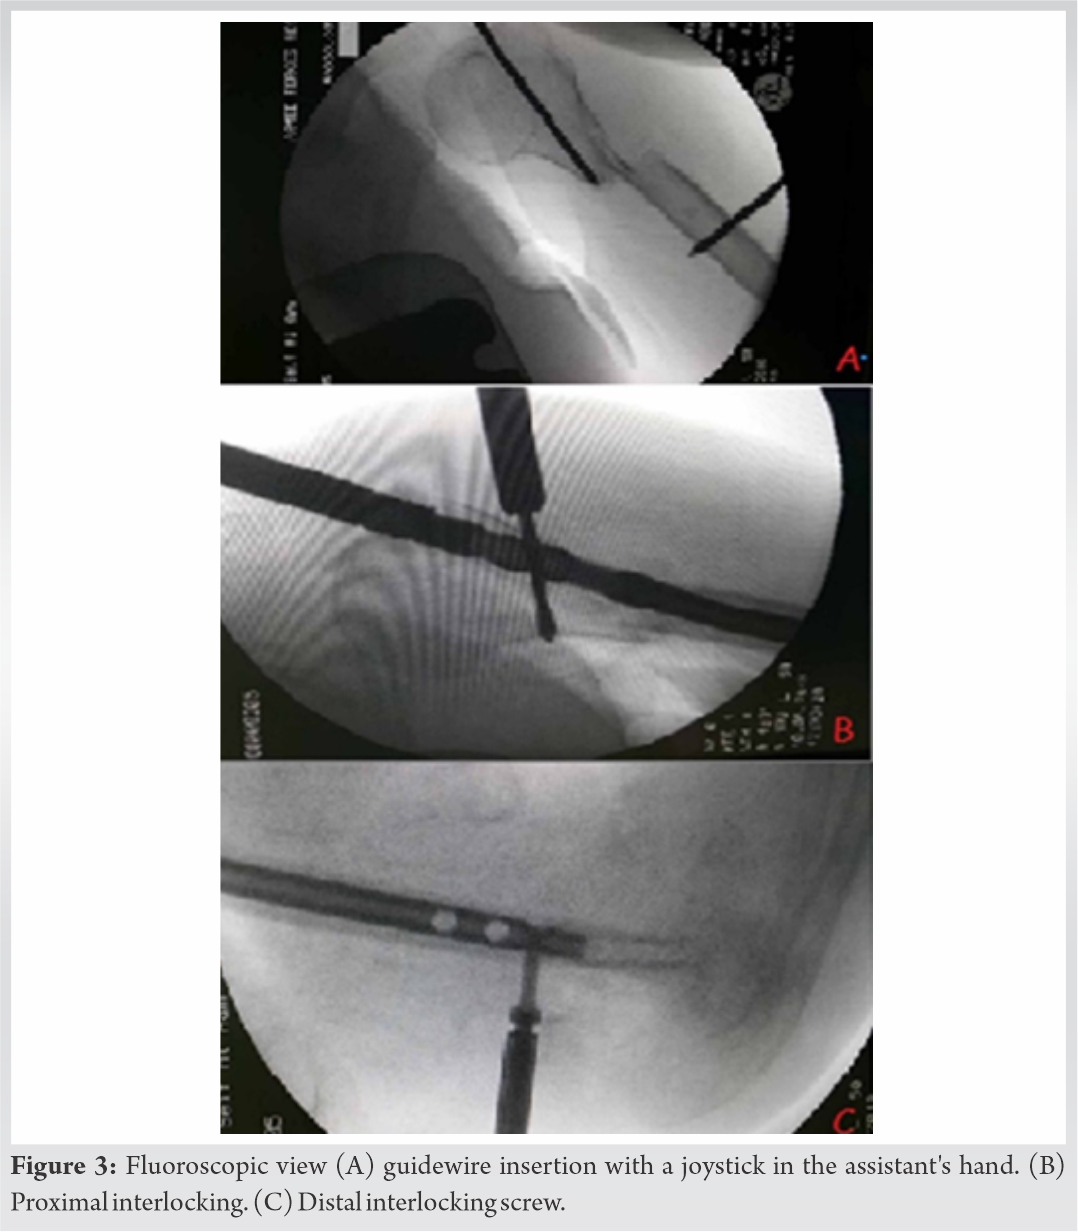

After passing the nail over the guidewire and confirming its position with fluoroscopy, proximal locking was cautiously performed using the jig because of the proximity of the axillary nerve (Fig. 3).